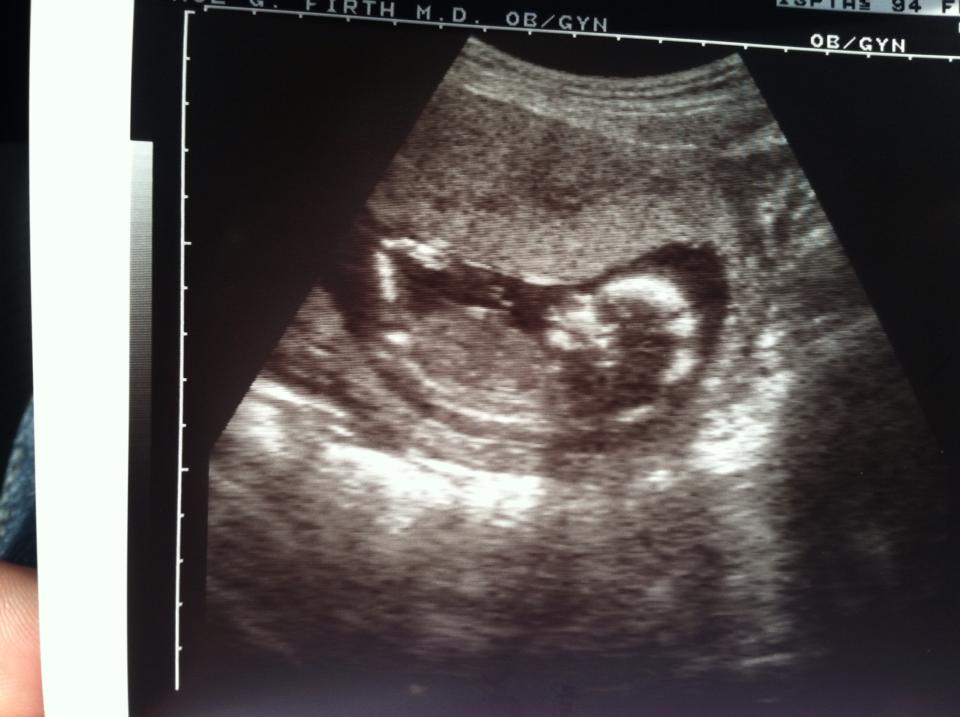

14 weeks 2 days. They wouldn't even guess. No potty shot.